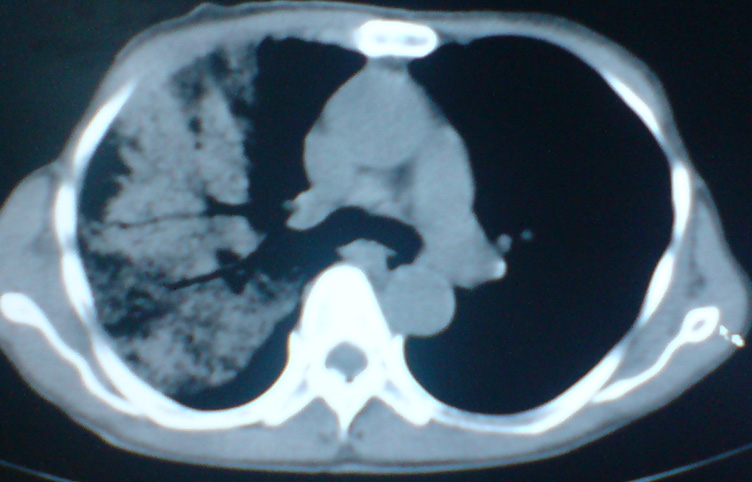

患者,女,60岁,右侧胸痛、咳嗽两个月。

首先考虑肺泡癌。

典型的细支气管肺泡癌

支持:大叶性肺炎,病灶内支气管走行自然,无僵直及粗细改变,建议抗炎治疗后复查!